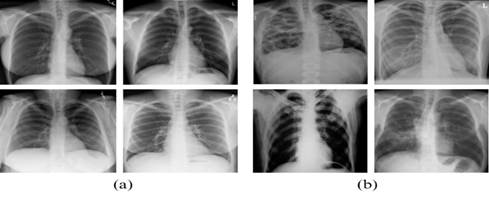

La Figura 2 presenta ejemplos de las radiografías pulmonares extraídas del conjunto de datos de Kaggle, incluyendo imágenes de pacientes sin indicios de tuberculosis como radiográficas que evidencias signos o patrones asociados a la presencia y posible progresión de la enfermedad.

Figura 2. Radiografías de pulmón sin afectaciones (a); Radiografías de pulmón afectado por tuberculosis (b).

Fuente: Kiran y Jabeen (2024); Rahman et al. (2020)